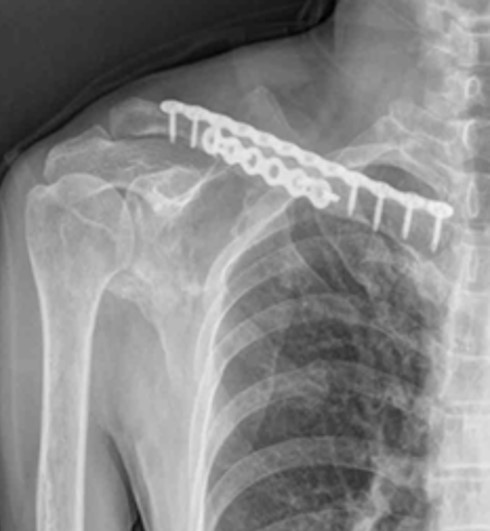

골절 치료는 주로 금속판, 금속정, 금속나사 등 골고정장치를 통한 수술적 치료가 일반적이지만, 이는 뼈의 단순한 연결만 제공할 뿐 실제 재생 속도는 더디어 환자의 일상 복귀에 많은 시간이 소요됩니다.

초기 금속판 이식

불유합 및 금속판 변형

늦은 뼈 재생속도로 인한 금속판 변형 및 재수술